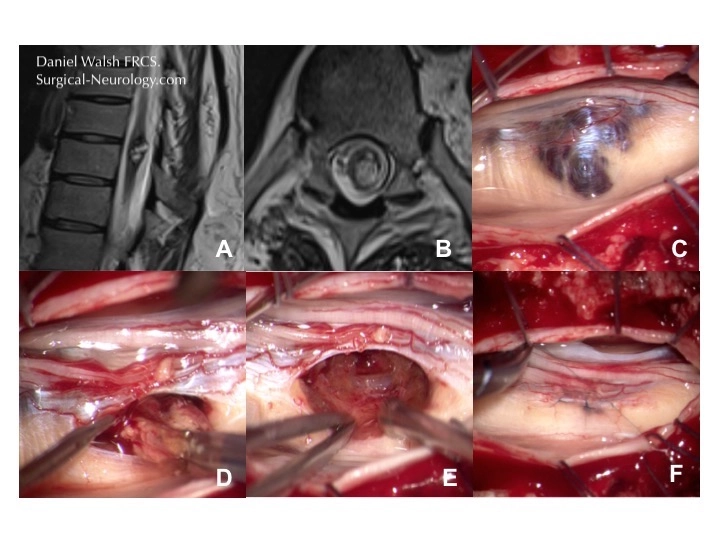

In the illustration below panels A and B show a lower thoracic intramedullary cavernoma first on axial and then sagittal plane MR scans. Panel C shows the localisation of the cavernoma within the cord with ultrasound as it is not visible on the surface of the cord (D). The cord is opened in the midline between the dorsal columns in this case to gain access and remove the cavernoma (F-H)

No attempt is made to remove the golden coloured nervous tissue surrounding the malformation. In the spinal cord such dissection is very likely to affect function and it is prudent to leave it be. Once satisfied that the cavernoma has been completely removed the incisions are closed with tiny sutures, thinner than a hair. This reconstruction of the spinal cord is shown below where the cavernoma is accessed via the sensory nerve root instead of disturbing relatively unaffected dorsal columns.

Once satisfied that the cavernoma has been completely removed the incisions are closed with tiny sutures, thinner than a hair. The very best of outcomes will usually mean that there is a temporary disturbance of ones ability to co-ordinate movements, affecting the ability to walk or use the hands. For most uncomplicated cases this will gradually recover. There is always a risk of new deficit however that must be consider beforehand. In the example below the cavernoma has erupted through the surface of the spinal cord but the normal structure is restored after closure.